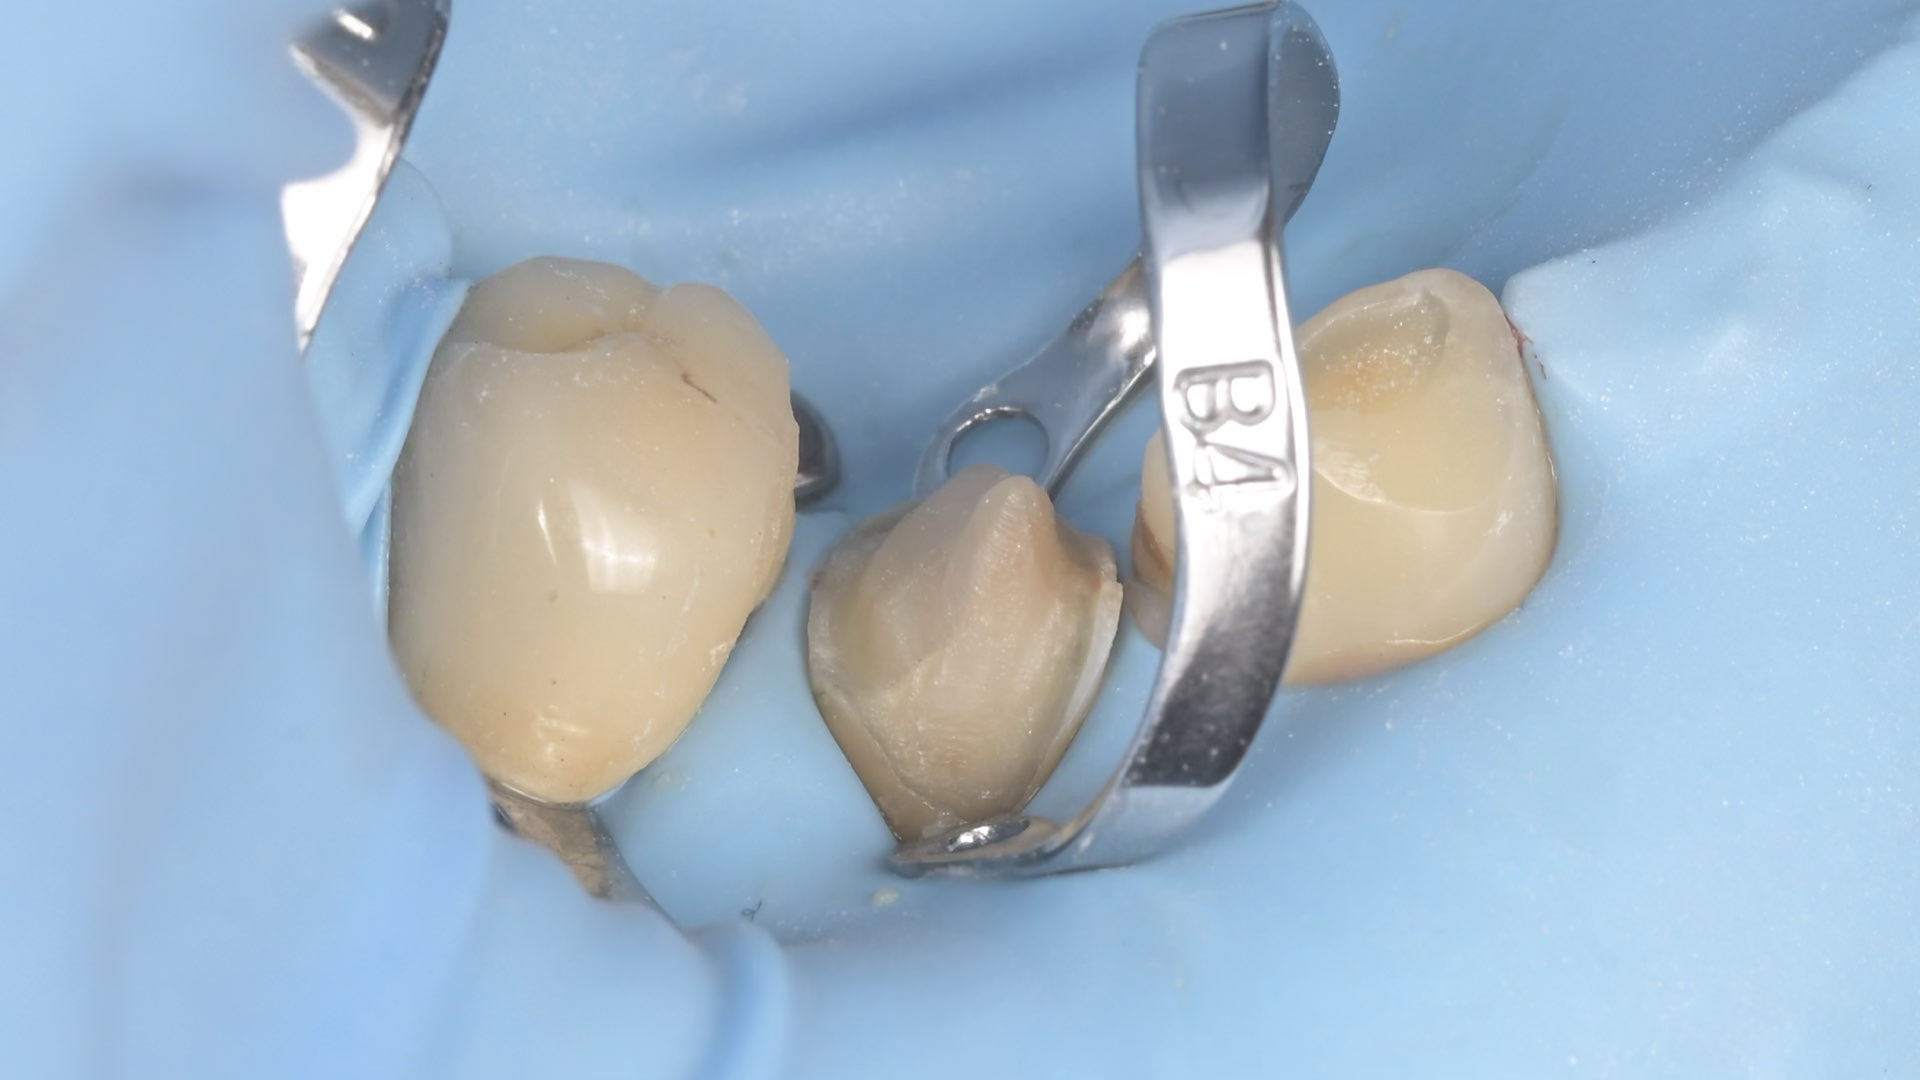

A biomimetikus fogászat egy modern megközelítés, melynek célja, hogy a fogak helyreállítását a fogorvos a természetes fog szerkezetét utánozva végezze el. A módszer kulcsa, hogy a fogat a lehető legkevésbé invazív módon kezelje, maximalizálva a megmaradt egészséges fogszövetet.

Célja, hogy az elkészült tömések és betétek (inlay, onlay) ugyanolyan erősek és rugalmasak legyenek, mint a természetes fog.

Ennek eléréséhez speciális ragasztási technikákat és bio-kompatibilis, üvegszál-erősítésű anyagokat használnak, melyek szorosan kötődnek a foghoz.

A hagyományos koronázással szemben, ahol sok ép foganyagot kell eltávolítani, a biomimetikus eljárásnál csak a sérült részeket távolítják el.

Ez segít megelőzni az úgynevezett „mély tömések” okozta gyökérkezelési szükségletet, mivel az ideg a fogban kevésbé sérül.

A megmaradó erős fogszövetnek köszönhetően a helyreállított fogak sokkal ellenállóbbak a repedésekkel és töréssel szemben.

A rágóerők egyenletesebben oszlanak el, így a fogat kevesebb stresszhatás éri rágás közben.

Ez a megközelítés hosszú távon stabilabb és tartósabb eredményt biztosít, csökkentve a jövőbeni fogászati beavatkozások szükségességét.

Összefoglalva: Az így elkészült tömések időtállóbbak, pontosabbak és jobban védik a megmaradt foganyagot, mint a hagyományos technikával elkészített tömések, a kutatások alapján, ez a jelenlegi ismereteink szerinti legmodernebb, evidence-based eljárás.